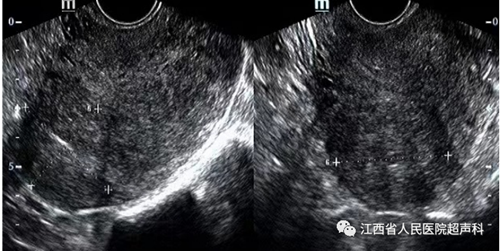

超声检查是公认的首选检查,能准确的观察到子宫的大小、形态,肌瘤的有无。MRI检查能发现直径0.3 cm的肌瘤,对于肌瘤的大小、数量及位置能准确辨别,是超声检查的重要补充手段。经阴道超声检查最常用。但对超出盆腔的肿物、肥胖及无性生活女性适用传统的经腹壁超声检查。

超声引导下微波消融术是利用微波的局部致热效应,在短时间内使针型辐射器周围的组织温度升高至可以使组织细胞蛋白质发生凝固性坏死的高温,造成组织细胞不可逆性凝固坏死,实现在保留子宫基础上达到子宫肌瘤组织和细胞原位灭活、肌瘤缩小或经自然腔道排出体外完全消失的治疗目的。